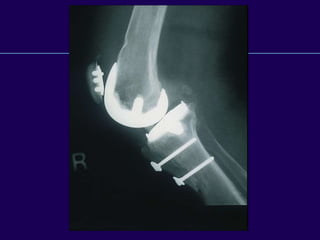

Complications in Total

Knee Arthroplasty

Periprosthetic Fractures

Infected Total Knee

Arthroplasty

Supracondylar

Fractures of the

Femur

After Total Knee

Supracondylar Fractures

After TKR

l Notching of the femoral cortex

l Osteoporosis

l Prolonged steroid use

l Preexisting neurologic

disorders